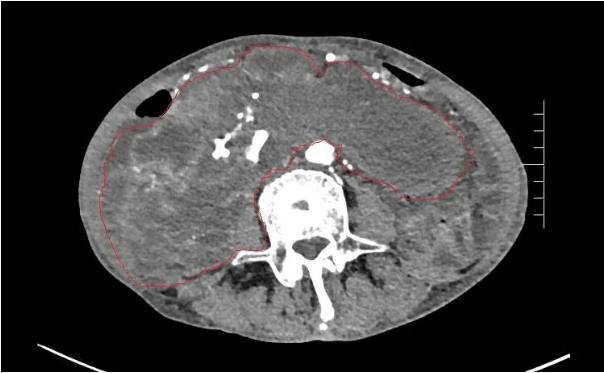

患者王大爷,男,72岁,发现腹腔肿物10余年,近两年来患者双下肢乏力、贫血,依靠间断输血维持着正常生活,出现头昏,行动困难,腹部疼痛及便血慕名来我院就诊。入院后查体评估患者年龄大,体质差,严重贫血,肺部感染及肠梗阻征象,腹部增强CT检查提示腹膜后巨大肿瘤,长径超过30厘米,占据大部分腹腔,并可能存在双原发肿瘤。

苗满园肿瘤外科团队在麻醉科/手术室的紧密配合下为该患者进行手术,术中发现肿瘤巨大,几乎占据了整个腹腔,从左侧向右腹腔延伸,向上将肝、肾挤向膈下,向左将胃及小肠挤向左上腹,向下深达盆腔内,包绕下腔静脉、肠系膜上动脉等大血管及输尿管,回盲部及回肠也受侵犯。手术难度巨大,风险极高。团队凭借着高超的手术技能和精准的手术预案沉着应对,迎难而上,应用高频电刀、超声刀、切割缝合器等先进设备,耗时近5小时为患者切除了巨大腹腔肿瘤,并联合右半结肠切除,术中出血仅50ml。术后病理为腹膜后巨大平滑肌瘤+回肠腺癌。